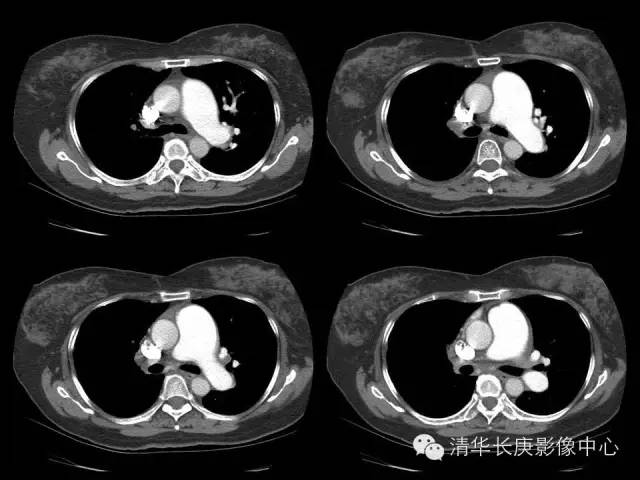

【病例】先天性单侧肺动脉缺如1例CT影像表现